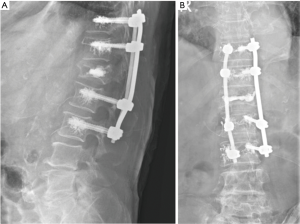

All the nine patients were in theory suitable for corpectomy and expandable titanium cage implant (7). But this approach was performed only in two of them. In fact, in 7 patients, a reconstruction of the anterior and medial spinal column was accomplished by third generation percutaneous vertebral augmentation systems (MK). In all the cases however a posterior fixation with rod and screws was always performed. The choice between one technique and the other one was made according to the signal in short tau inversion recovery (STIR) in the MRI sequences: in case of hyperintense signal to the level of the collapsed vertebra (VP), we decided for the percutaneous vertebral augmentation (Figures 3,4) (8). In absence or in case of very low STIR hyperintense signal, we chose for the standard corpectomy (Figures 5,6). Indeed, the presence of positive signal in the VP is in fact indicative of the reducibility of the vertebral soma. Moreover, in the cases of spinal canal compression the applicability of the third generation MK alone, without any posterior decompression, must not be excluded: it must be inferior to 1/3 and 2/3 respectively in case of fractures level above and below the spinal cord and any clinical signs of radicular compressions must not be identified. Otherwise, a direct posterior spinal cord decompression must be performed. Furthermore it is mandatory to evaluate the state of the anterior longitudinal ligament (ALL). In case of ossification of ALL at the level of the VP, MK has to be avoided, because a satisfactory correction of the vertebral height and a substantial management of the regional deformity might not be achieved. Mean follow-up was 18 months (range, 12–28 months). None of the patients experienced neurologic deterioration neither they showed a progression of local or regional deformity. No infections, dural tears, or spinal cord injuries occurred. No revision surgery was performed. In case of corpectomy the main blood loss and the mean surgical time were inevitably greater (9).